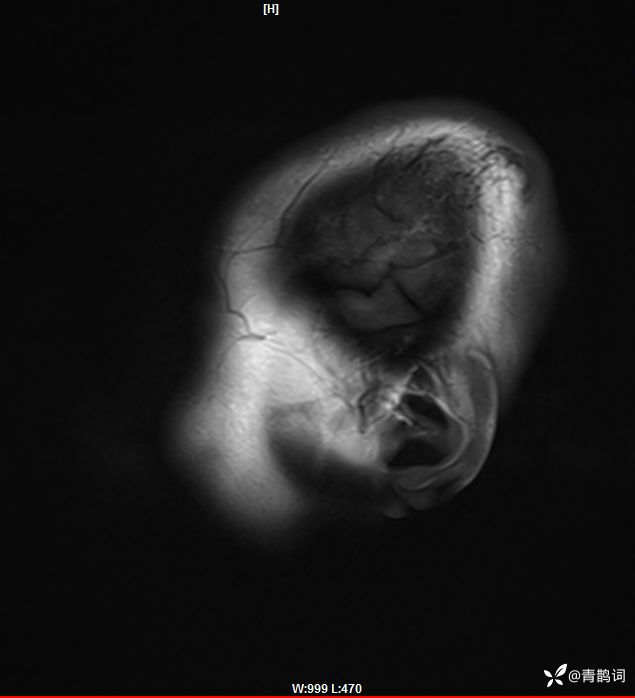

病例分享 | 45岁女患,7年的病史,结合影像学,如何诊断?

1、患者:女, 年龄:45岁

2、主诉:走路不稳渐加重7年,饮水呛咳伴头晕2年渐加重。

3、简要病史:患者于入院前7年出现走路不稳,表现为行走右偏,逐渐加重,易跌倒、不能自理;近2年出现饮水呛咳、吞咽困难及头晕;病程伴有耳鸣、反应迟钝,无恶心、呕吐。既往否认高血压、否认糖尿病、否认冠心病。

4、体格检查:体温36.0℃,脉搏80次/分,呼吸20次/分,血压140/70mmHg。查体:神清,构音障碍;眼球运动自如,双水平性眼震,左视时明显;双侧瞳孔等大同圆,左:右=3mm:3mm,对光反射灵敏;双侧额纹对称,双侧鼻唇沟对称;伸舌居中;四肢肌力4级,肌张力减低,四肢腱反射亢进,双侧Babinski征阳性;粗测感觉未见明显异常;四肢共济运动完成差,左侧为著;脑膜刺激征阴性。

入院后完善磁共振:

FLAIR: